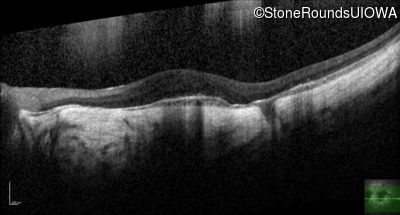

Optical Coherence Tomography - Left - 20/25 +2

Exemplar / OCT Stack

OCT Stack